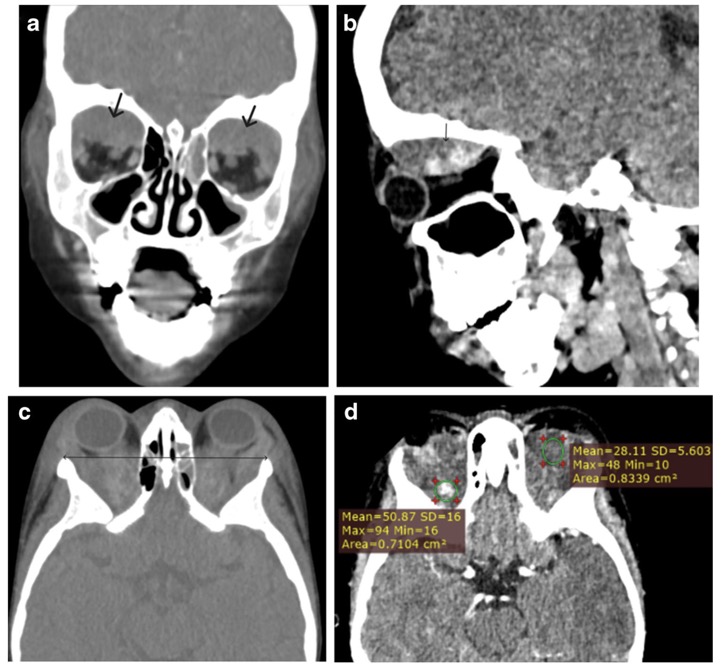

Hématomes sous-périostéaux bilatéraux

Les infarctus osseux peuvent parfois impliquer l'orbite lors d'une crise vaso-occlusive

=> hématomes sous-périostéaux

Diagnostic: CT C+ exclut infection

TRT: décompression chirurgicale